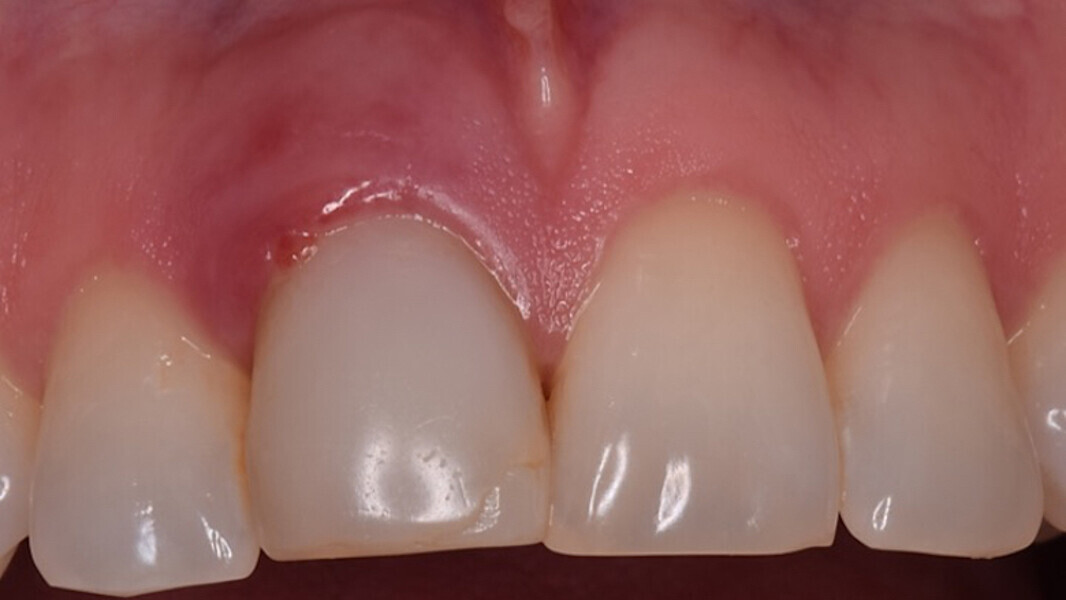

Figura 18. Imagen a los 3 meses al retirar la corona provisional. Obsérvese el grosor del margen gingival debido al uso del pilar cóncavo y la presencia de algunas partículas de biomaterial dentro del tejido blando. Estas partículas realizan una fibrointegración en el tejido conectivo que produce la estabilidad de estos tejidos durante años.